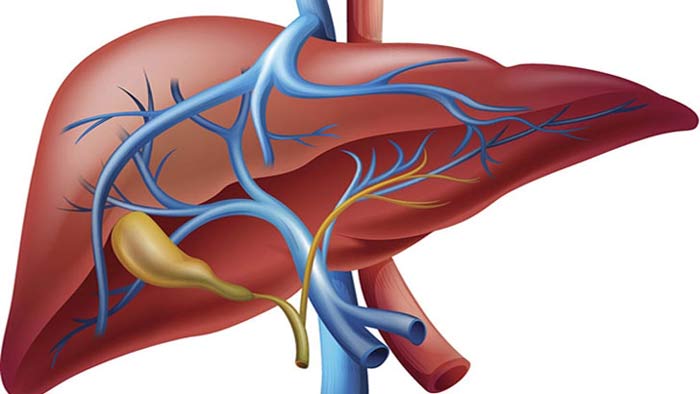

লিভার আমাদের শরীরের গুরুত্বপূর্ণ একটি অঙ্গ। শরীরে রক্ত পরিশোধন, শরীর থেকে টক্সিন বের করে দেওয়া, হজমের জন্য পিত্ত উৎপন্ন করা, শরীরে ভিটামিন এ, ডি, ই-সহ বিভিন্ন উপাদান ধরে রাখার মতো গুরুত্বপূর্ণ কাজ করে লিভার।

কার্যত শ্বাস নেওয়া ছাড়া শরীরের সব কিছু করতে লিভার গুরুত্বপূর্ণ। অর্থাৎ এটি আমাদের শরীরে ৫০০টিরও বেশি কাজ করে থাকে।